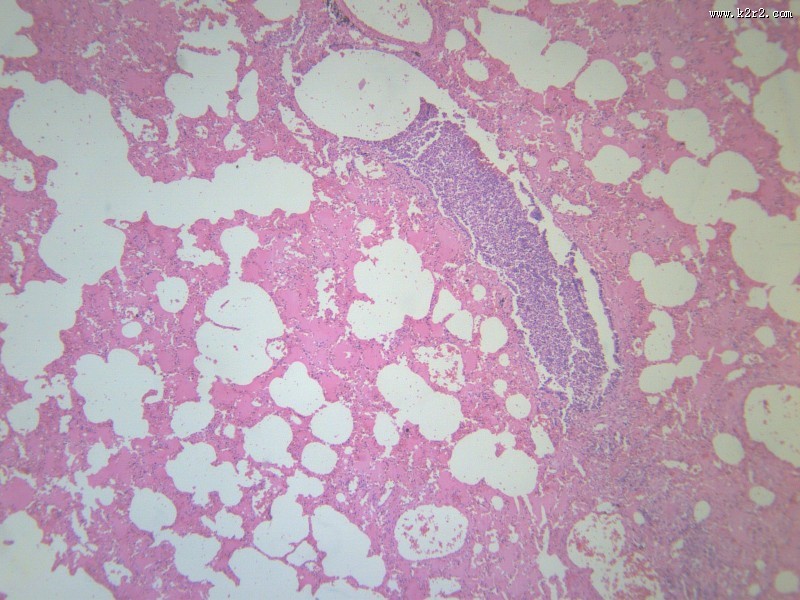

小叶性肺炎 - 第8张 共有

显微切片

炎症

肺炎

bronchopneumonia

小叶性肺炎

支气管肺炎